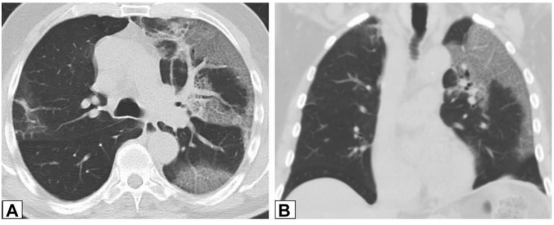

在活检证实的OP患者中,中肺(图2A)和下肺(图2B)的增强CT扫描图像显示双侧多灶性支气管血管周围实变灶。

图2 支气管血管周围实变

图源:Chest, 2022, 162(1):156-178.图3A为71岁男性,2011年7月因劳力性呼吸困难就诊,胸片显示右肺上叶实变。图3B为2012年6月再次检查显示右肺上叶异常已消失,左肺出现广泛实变。图3C为2013年6月,左肺病变消失,但右肺下叶出现新的实变。这些发现是典型的OP游走性表现。图源:Chest, 2022, 162(1):156-178.图3所示患者胸部CT可见磨玻璃影伴小叶间隔增厚和铺路石征的游走灶(图4)。由此可见,OP的实变可以发生在肺的任何部位,边界清晰或模糊,呈游走性特点。图源:Chest, 2022, 162(1):156-178.OP的实变可以呈局灶性、多发性和弥漫性,也可以表现为结节或肿块。图5所示患者为70岁女性,COVID-19确诊9个月后出现持续气促,CT平扫图像显示支气管血管周围多灶性肿块样实变。在类固醇治疗后症状显著改善,实变消退,推测诊断为OP。图源:Chest, 2022, 162(1):156-178.实变常伴支气管充气征,可伴散在的磨玻璃样低密度或小实质结节。以主要的或完全的磨玻璃低密度为表现者较少见。图6A所示为一名有甲状腺乳头状癌病史的47岁男性患者碘131治疗4个月后的CT平扫图像,可见右肺上叶支气管血管周围磨玻璃影。PET/CT扫描显示磨玻璃影代谢增高(图6B)。CT平扫图像显示左肺上叶新出现的磨玻璃影(图6C)。支气管活检结果与OP相符。图源:Chest, 2022, 162(1):156-178.图7为一名71岁男性患者因使用胺碘酮导致SOP的CT平扫图像,可见左肺广泛磨玻璃影,小叶间隔增厚(铺路石征)。磨玻璃低密度影合并小叶间隔增厚可表现为铺路征。